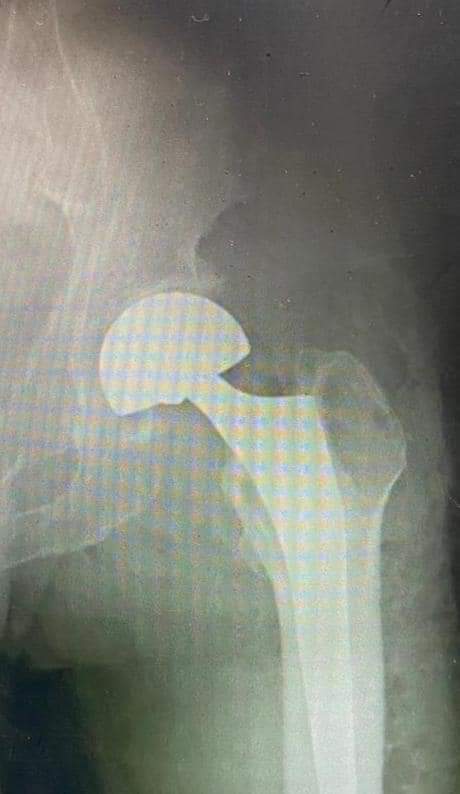

وطنا اليوم -  يقوم بعمليات تثبيت الكسور المعقدة بشكل طاريء وتبديل المفاصل بشكل مبرمج  مما خفف على المواطنين البحث عن أسرة في مستشفيات مركزية رغم صعوبة عمليات العظام من الناحية التقنية في المستشفيات النائية  إضافة الى  استقبال اعداد كبيرة بالعيادات ومعالجة جميع المرضى بالطرق المثلى انه الدكتور الانسان البارع والمتميز يزيد البريزات طبيب العظام في مستشفى الاميرة سلمى / ذيبان عيادة العظام  علماً بأنه كان  مستشفى تحويلي منذ تاسيسه والدكتور البربزات وقبل اربع سنوات في عام 2020  منذ انتقاله للمستشفى يقوم بهذه العمليات ومن بينها  عمليات نوعية لمرضى يعانون من كسور معقدة في الترقوة واجراء عمليات دقيقة ومعقدة لكسور لمرضى في مختلف أنحاء الجسم وعمليات تثبيت الكسور المعقدة وتركيب المفاصل وغيرها الكثير  والديسك " وآلامه وتبعاته وعلاجه وإجراء عمليات معقده وصعبه.

وأجرى الدكتور البريزات عمليات كبرى في جراحة العظام والتي تحتاج إلى مراكز متقدمة ومتطورة. وكذلك العمل على تثبيت أغلب انواع الكسور بطريقة طارئة وتبديل المفاصل بطريقة مبرمجة بما يتناسب مع امكانات المستشفى والتي هي  جزء من  العمليات الدورية بمستشفى الاميرة سلمى في ذيبان  والتي تخفف العبئ على المستشفيات المركزية وعلى المواطن في آن واحد.